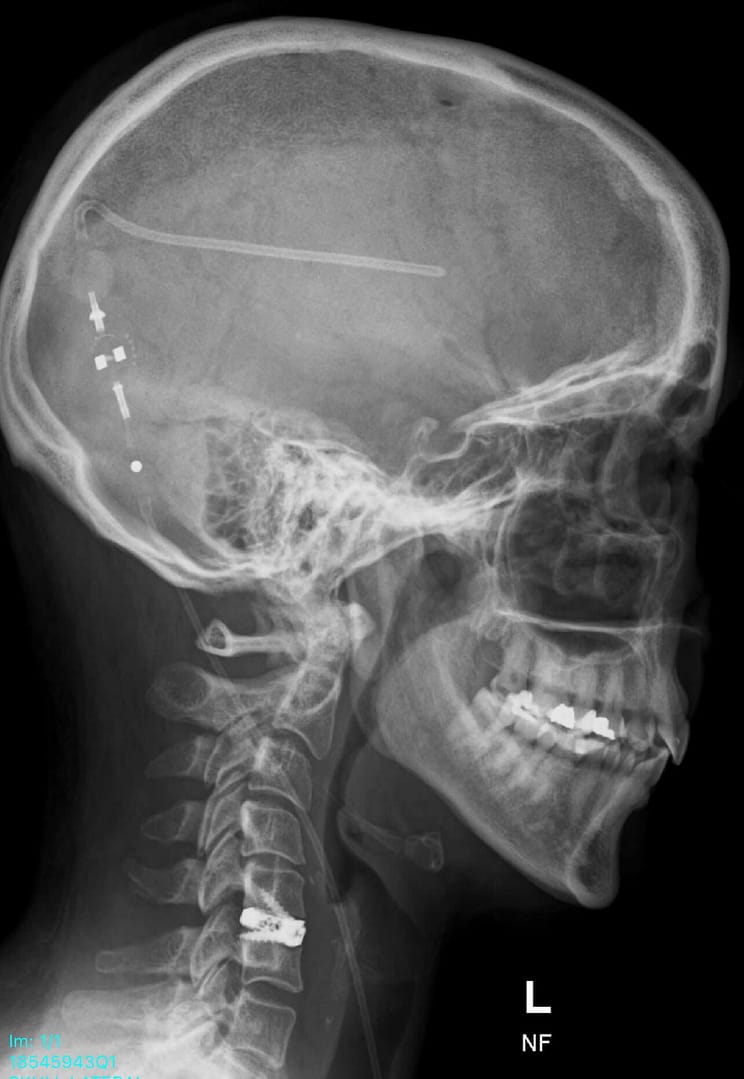

The pain from my incisions only became evident the following day, once I was back in the ward. Running my fingers down my head, over my neck and chest, it felt very tender to touch. Undoubtedly, it was from the tunnelling of the shunt tubing from my head down to my abdomen. I have an incision to the right of my belly button (Just under 8cm long), small scar above my left eye (from the stealth machine), incision down my neck (under my right ear) and a half moon shaped one, on the back of my head. My shunt valve is on the right-side of my head, at the back, slightly higher than my right ear. Working alongside my ETV, which is still wide open.